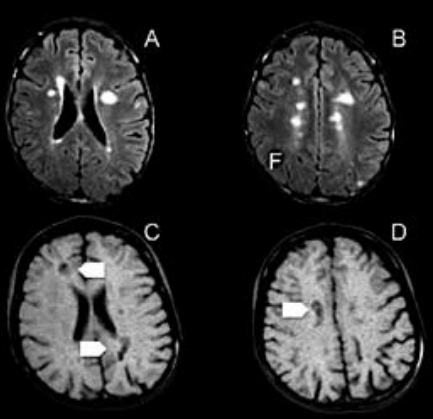

As imagens da ressonância abaixo são sugestivas de: